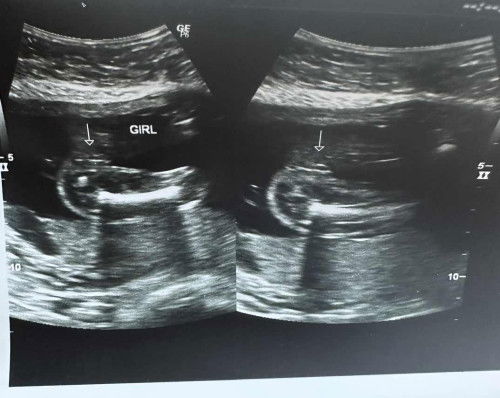

Just wanted to share our baby's CAS, everythings normal naman daw and we're having a girl! By the way, sure na kaya yung gender pag CAS? I'm 21 weeks nung nag pa cas ako.

mukhang girl, based sa image. may BPS pa naman. makikita ulit ang gender dun.